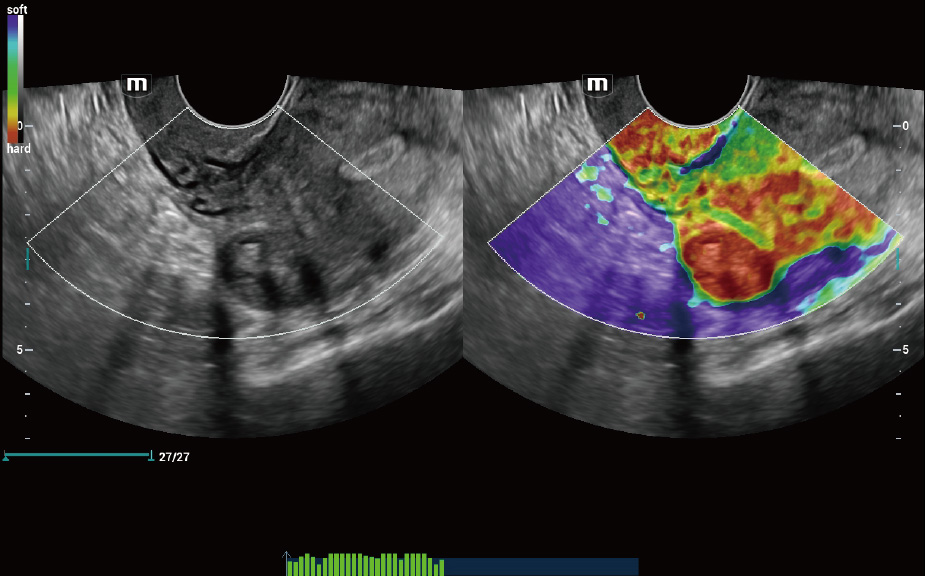

Scenario-oriented Full-stack Intelligence

The innovative Smart Scene 3D solution enables automated identification of tissue characteristics and delivers organ-specific diagnosis with full-stack intelligence throughout the entire procedure. This innovation reduces dependence on clinical skills, while elevating diagnostic accuracy, confidence, and efficiency.